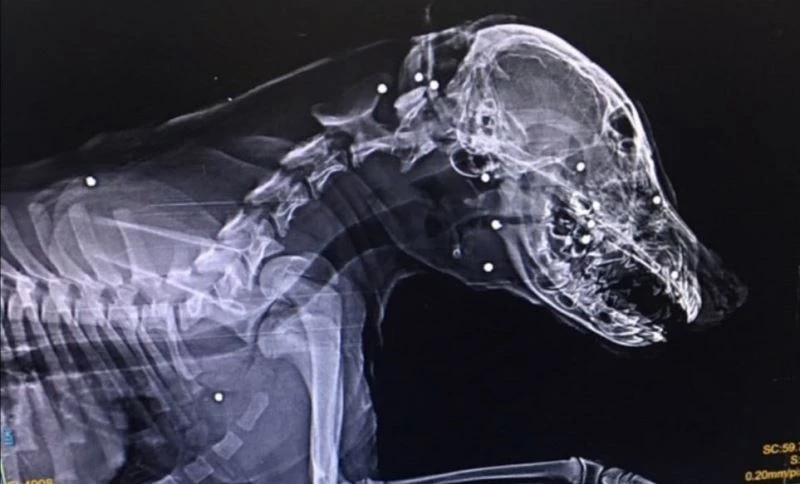

Zonguldak’ın Devrek ilçesinde sahipli bir köpek kimliği belirsiz kişilerce tüfekle suratından vurularak ağır yaralandı.

Edinilen bilgiye göre, Zonguldak’ın Devrek ilçesinde Mert Ekşi’ye ait aylık sahipli köpek kimliği belirsiz kişi veya kişilerce tüfekle suratından vurularak ağır yaralandı. Devrek Mekekler Caddesinde meydan gelen olayla ilgili Devrek Emniyet Müdürlüğüne şikayette bulunan Mert Ekşi, ”Bunu yapanlar insan olamaz bu hayvanı ateş ederek yaralayanların bulunmasını ve adalet önüne çıkarılmasını istiyorum” diye konuştu.

Tedavisi için köpeğini aracıyla Zonguldak’a götüren Ekşi’nin köpeğini vuran veya vuranlar için polis geniş çağlı soruşturma başlattı